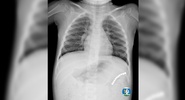

Врачи Детской городской клинической больницы № 9 Екатеринбурга спасли 5-летнюю Ульяну, которая проглотила 10 магнитных шариков.Московский Комсомолец Екатеринбург

После обследования маленькую пациентку прооперировали.Lenta.ru

По словам детского хирурга ДГКБ №9 Андрея Чукреева, связавшуюся цепочку магнитов достали, минимизируя риск осложнений.URA.Ru